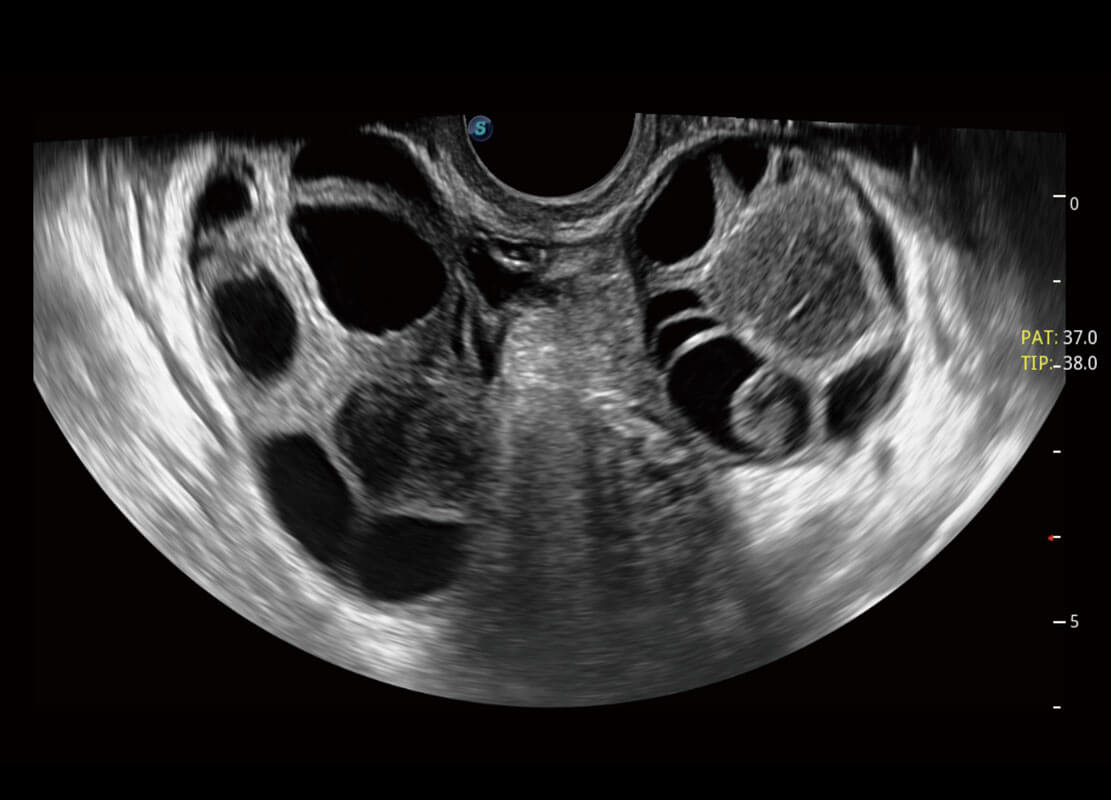

生殖健康

P60卓越的图像质量搭载专科探头,在妇科基础疾病的诊断、卵泡生长的监测、输卵管通畅情况的判别等方面为您提供全面的生殖应用方案。

• 腔内妇科-宫腔分离

• 腔内妇科-卵巢